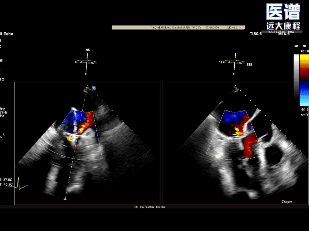

TEE

TEE-2D血流

重度DMR,LVEF 61%,LVIDd 5.62cm,LVIDs 3.27cm,VCW 0.72cm,EROA=0.47cm2;RV=83ml,PG mean 3mmHg,PASP 51mmHg。

病变位置为:A1邻近交界处脱垂;宽度/高度:1.08cm/0.29cm;A1/P1瓣叶长度:1.38cm/1.17cm;前后径(AP直径):3.56cm;二尖瓣口面积:4.39cm2